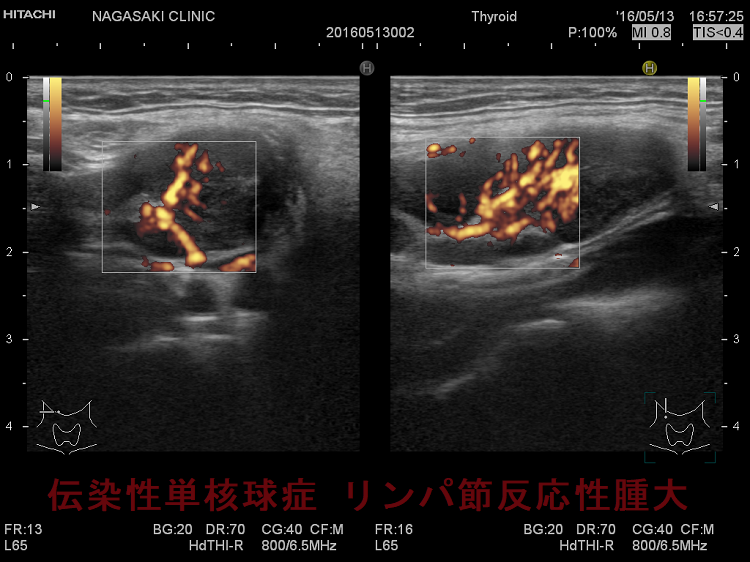

亜急性甲状腺炎と鑑別を要する伝染性単核球症。喉(のど)の痛みと首のリンパ節の腫れを甲状腺の病気と思って、長崎甲状腺クリニック(大阪)を受診される方がおられます。

- 痛みを伴う著明な後頸部リンパ節腫脹は1〜2週頃がピークで、耳下腺の下、外側頚部まで累々と広がり、全身のリンパ節も腫大します。

- 亜急性甲状腺炎と鑑別を要する伝染性単核球症を発症